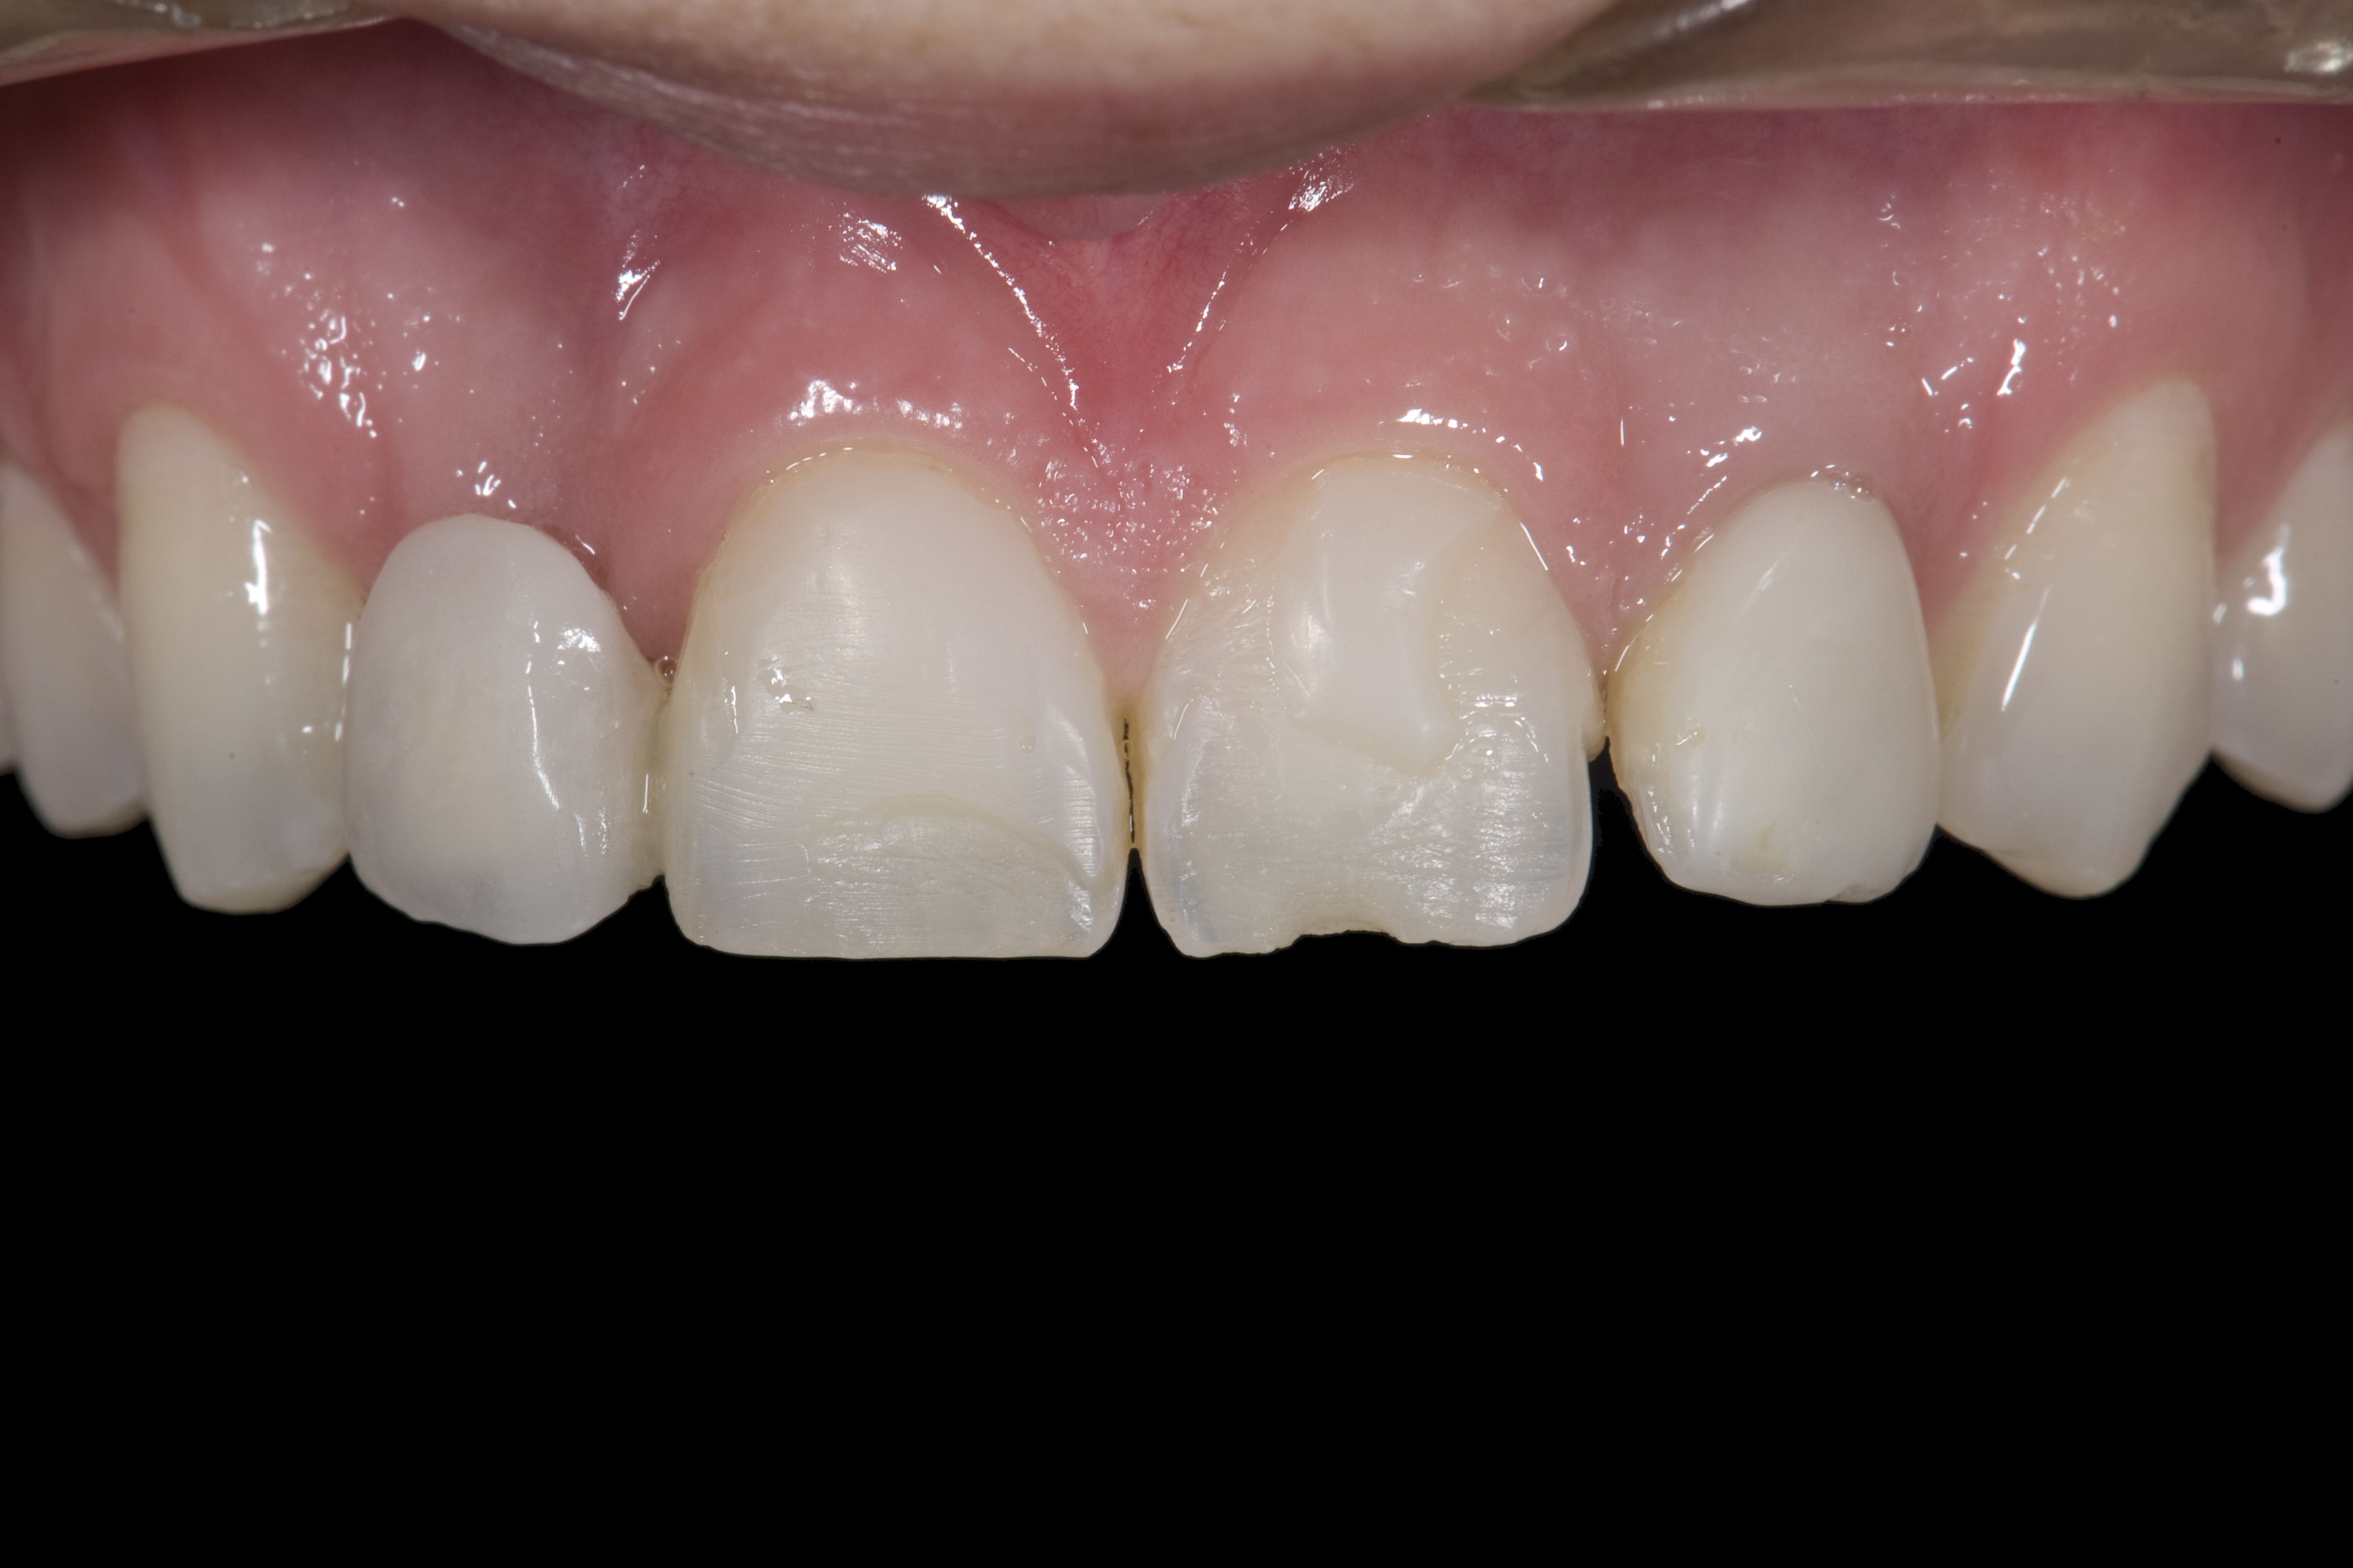

(20.) Facial view of final single-wing, modified zirconia resin-bonded bridges.

Figure 20

(21.) Smile view.

Figure 21

When the patient returned, the fit was evaluated in the mouth. Once verified, the internal surface of the framework was etched with a 9.5% hydrofluoric acid for 90 seconds and then salinized. After etching the enamel surface with phosphoric acid for 30 seconds and applying the primer (Single Bond Plus, 3M ESPE) to both the internal surface of the framework and the enamel, the zirconia bridge was bonded with a dual-cure resin cement (RelyX™ ARC, 3M ESPE). After the procedure, the patient ended up with a long-term, high-strength esthetic restoration advantaged by the bonding potential of fledspathic ceramic (Figure 20 through Figure 24). Six years after placement, the prosthesis had remained in place with no complications.

Some patients do not want an implant due to the need for surgical intervention, and others may not have enough space for implant placement. A 15-year-old patient presented to the office after completion of orthodontic treatment to idealize the spacing of her teeth and improve her occlusal relationship (Figure 12 through Figure 14). Because both of her maxillary lateral incisors were missing, the patient was wearing a retainer with lateral incisor pontics. She had a busy school schedule, but expressed her desire for a fixed restorative option. All of her options were discussed, and the patient was informed that if she wanted an implant, she would have to wait for at least 3 to 4 years for completion of growth. The patient was not sure if or when she wanted to have an implant placed in the future, especially considering her busy schedule and desire to attend college after high school. Considering her age and the need to be conservative, a single-wing zirconia Maryland Bridge was chosen as the ideal prosthetic replacement option. Because bonding a non-etchable and smooth surface such as zirconia requires chemical adhesion, it was decided to use a modified technique to make the bridge more retentive. One of the ways to improve adhesion of a zirconia bridge is to use an etchable feldspathic ceramic layer on the internal surface of the zirconia retainer.56-58 Unfortunately, it can be difficult to determine the thickness of the ceramic and ensure accurate seating of the restoration.